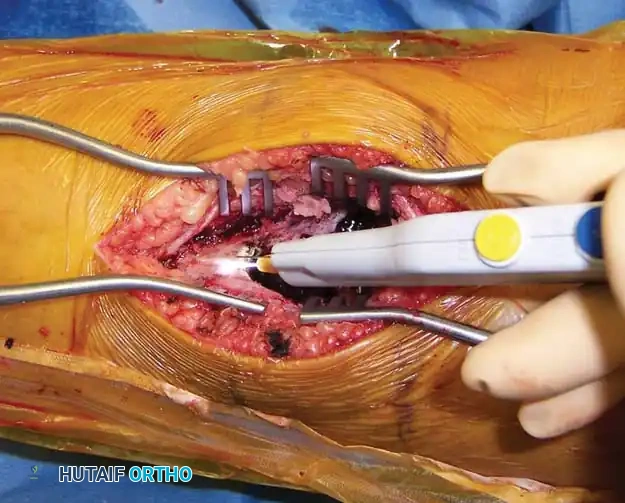

- High-Speed Burr (Extended Curettage): Standard curettage alone leaves microscopic reactive tissue in the bony interstices, leading to high recurrence rates. A high-speed power burr is systematically used to remove an additional 1-2 mm of bone from the entire cavity wall, extending the margin into normal-appearing cancellous bone.

Following the removal of the gross cyst lining with large curettes, the tumor cavity is systematically enlarged and cleared using a high-speed power burr.

- Adjuvant Therapy: To further eradicate microscopic disease, a chemical or thermal adjuvant is applied. Argon beam coagulation is highly effective, providing uniform thermal necrosis to the cavity walls while minimizing deep tissue damage. Alternative adjuvants include liquid nitrogen (cryotherapy) or phenol, though these carry higher risks of adjacent nerve/tissue damage.

The tumor cavity is meticulously treated with argon beam coagulation to achieve thermal necrosis of any remaining microscopic cyst lining.